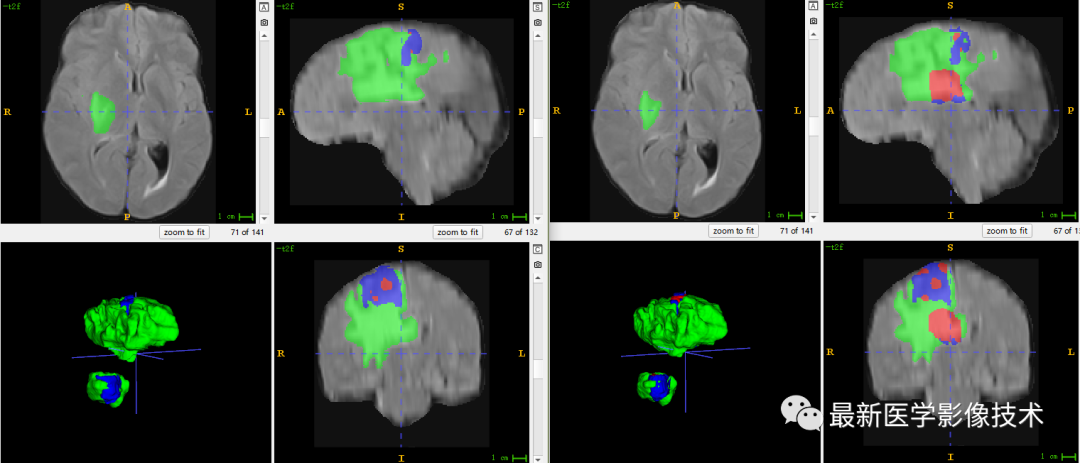

6、验证集分割结果

左图是金标准结果,右图是网络预测结果。

7、测试集分割结果